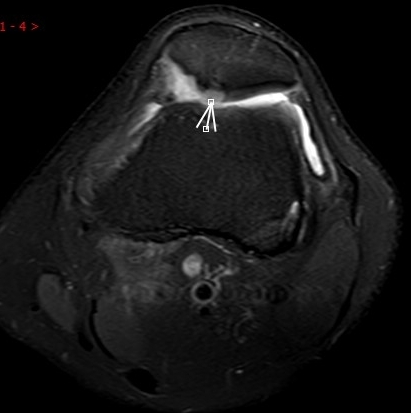

MRI偵查:揪出前交叉韌帶斷裂(呈“波浪狀”或連續(xù)性中斷)、內(nèi)側(cè)副韌帶損傷,防止關(guān)節(jié)“脫軌”

(內(nèi)側(cè)副韌帶損傷)